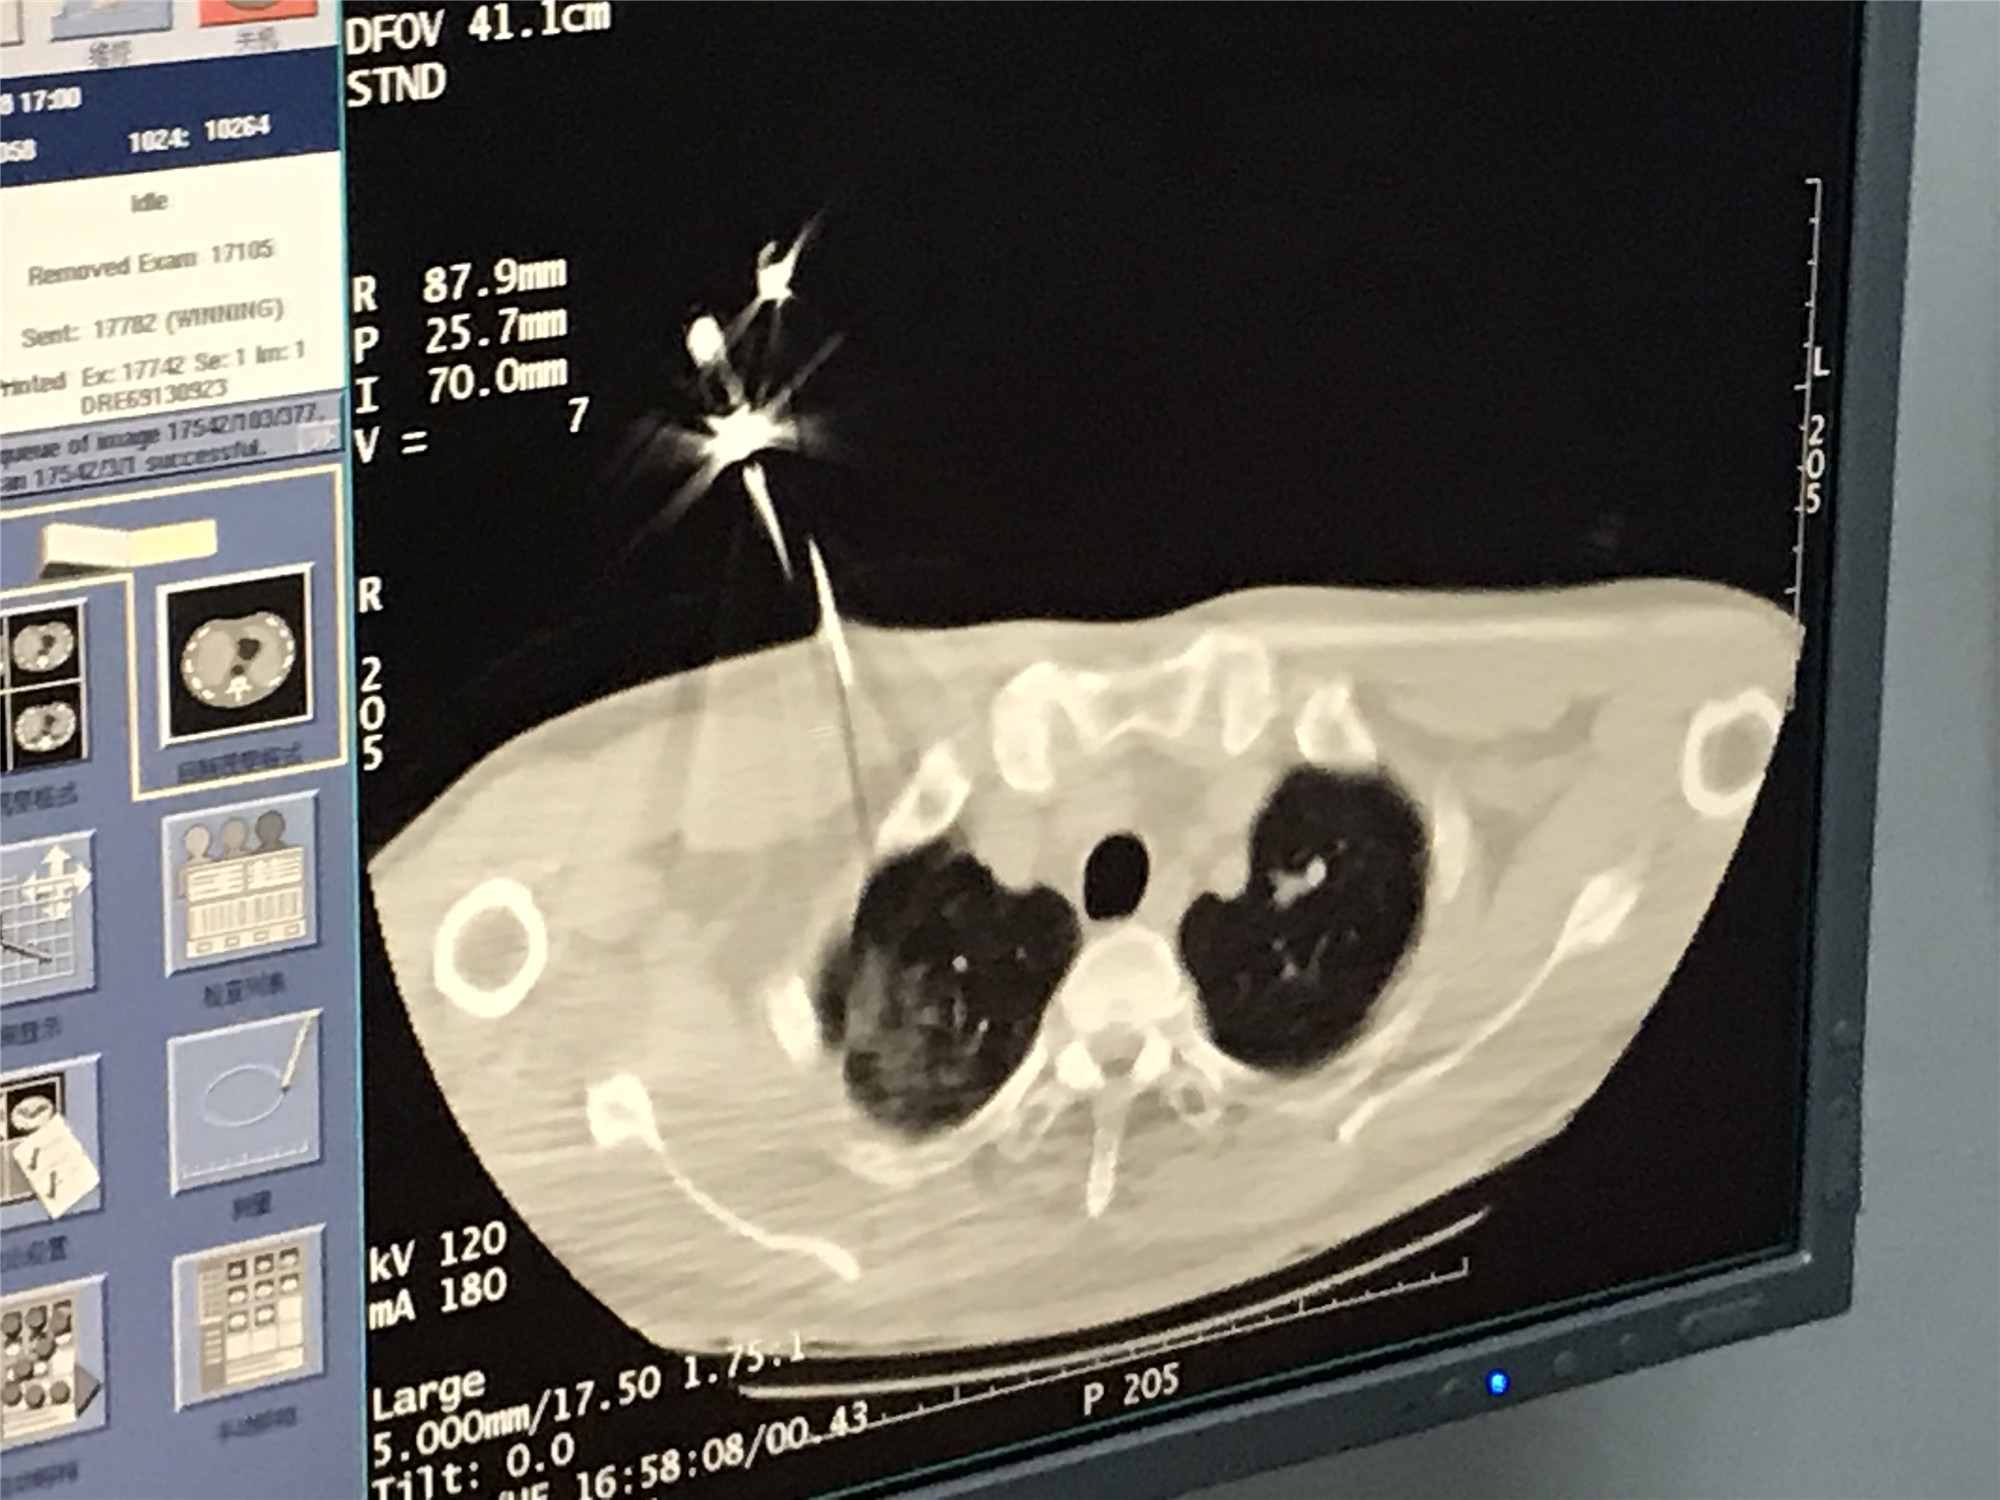

2021年1月份肺部氩氦刀手术